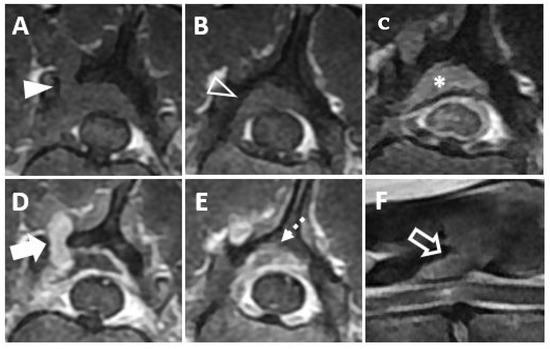

Thoracic radiography revealed a small, round soft tissue opacity in the right middle lung lobe (Figure 1A) and a lytic bone lesion adjacent to the articular facets between the thirteenth thoracic vertebra (T13) and first lumbar vertebra (L1). Abdominal ultrasonographic examination was unremarkable. Computed tomography (CT, Lightspeed, GE Healthcare, Milwaukee, WI, USA) was performed to evaluate the vertebral lesion and the mass in the lung, and CT images were obtained before and after intravenous administration of a contrast medium (Omnipaque 300; GE Healthcare, Milwaukee, WI, USA). A post-contrast CT scan revealed small soft tissue masses in the right middle lung lobe (Figure 1B) and left caudal lobe (Figure 1C). A small soft tissue mass caudal to the right kidney was also found (Figure 1D). Moreover, osteolytic changes of the vertebral lamina and pedicle of T13 were identified (Figure 1E).

Magnetic resonance imaging (MRI, 1.5T, Signa, GE Healthcare, Waukesha, WI, USA) was performed before and after intravenous administration of a contrast medium (Magnevist; Beyer-Schering Pharmaceutical, Berlin, Germany). The mass was identified at the bone lysis region on a transverse T1-weighted image (Figure 2A) and on a post-contrast, transverse T1-weighted image (Figure 2D). The mass was seen to be invading the vertebral canal on the transverse T1-weighted image (Figure 2B) and on the post-contrast, transverse T1-weighted image (Figure 2E). On the post-contrast, transverse T1-weighted image, the mass was found to be mildly compressing the spinal cord and contrast enhancement of the spinal cord parenchyma was identified, suggesting a mild inflammatory response to the mass (Figure 2C). On a sagittal T2-weighted image, hyperintensity of the spinal cord parenchyma was identified (Figure 2F). Based on CT and MRI findings, an extradural mass invading the vertebral canal was diagnosed. Surgical management of the mass was performed, with the informed consent of the owner, for palliation of hind limb paresis, despite the multiple masses involving pulmonary region.

Figure 1. (A Soft tissue opacity (arrowheads) in the right middle lung lobe on thoracic radiography. (B) Large mass of the right middle lung lobe and (C) small mass of the left caudal lung lobe (open arrowhead) on post-contrast transverse images. (D) Small mass (open dashed arrowhead) dorsal to the right kidney. (E) Osteolytic lesion (arrow) of the T13. (R: right, T13: the 13rd thoracic vertebra).

Figure 2. Magnetic resonance images showing a mass invading the vertebral canal and the spinal cord lesion are depicted. (A The mass appears iso-intense at the bone lysis region on a transverse T1-weighted image (arrowhead). (B) The mass can be seen invading the vertebral canal on a transverse T1-weighted image (open arrowhead). (C) The mass can be seen mildly compressing the spinal cord (asterisk) and contrast enhancement of the spinal cord parenchyma (dashed arrowhead) is visible on a post-contrast, transverse T1-weighted image. (D) Contrast enhancement of the mass (arrow) is shown on a post-contrast, transverse T1-weighted image. (E) The mass can be seen invading the vertebral canal on a post-contrast, transverse T1-weighted image (dashed arrow). (F) The mass (open arrow) between T13 and L1 causing hyperintensity of the spinal cord parenchyma is shown on a sagittal T2-weighted image. (T13: the thirteenth thoracic vertebra, L1: the first lumbar vertebra.).